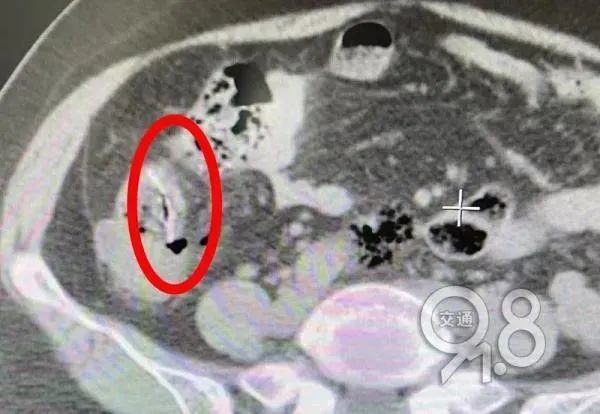

该院胃肠肛外科医生毛宗磊查体后发现她腹部压痛、反跳痛明显,肚子僵硬,血液检查显示白细胞严重超标,是腹膜炎的信号。腹部CT发现,胡大姐的小肠腔内有条状异物。

综合患者描述,医生判断其体内异物就是鱼刺,安排腹腔镜探查。在术中发现,胡大姐腹腔内已产生大量脓性腹水,回肠部有一根硕大的鱼刺穿破小肠,露出尖头,穿孔处的肠壁及系膜高度水肿。